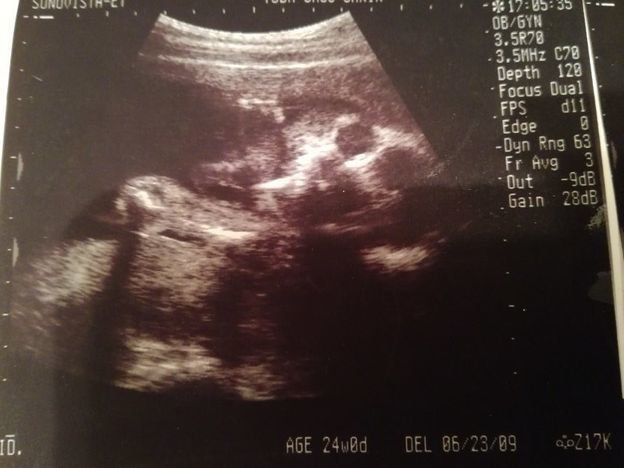

妊娠24週目のエコー写真

前回の妊婦検診から3週間後に出血して、この検診の前に慌てて受診したこともありました。原因は、“逆子”になっていた赤ちゃんに子宮を思い切り蹴られていたため。そんなこともありつつ迎えた、定期の妊婦検診。「出血はなくなりました」と先生に伝えたら、「赤ちゃんも逆子じゃなくなっているよ」と先生。ひとまず“逆子”がなおって良かったと主人にメールしました。